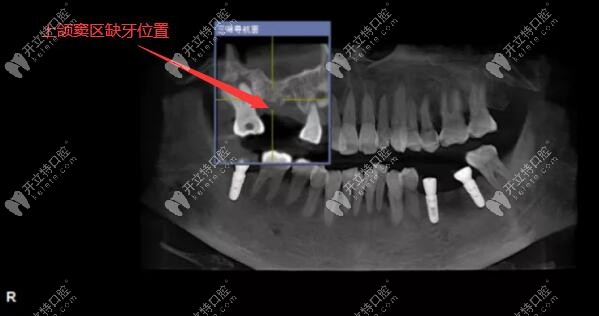

上頜后牙區(qū)骨量重度不足,做上頜竇外提升+同時植入種植體

牙槽骨量不足也能做種植牙哦~~~不信,來看51歲阿姨下頜后牙區(qū)骨量重度缺失,做上頜竇外提升的同時植入韓國奧齒泰種植體,是在深圳同步齒科做的哦!

今日分享:用3D數(shù)字化導(dǎo)板技術(shù)做上頜竇區(qū)的精準(zhǔn)種植牙案例,植入的是美國皓圣3508和4507型號的種植體。